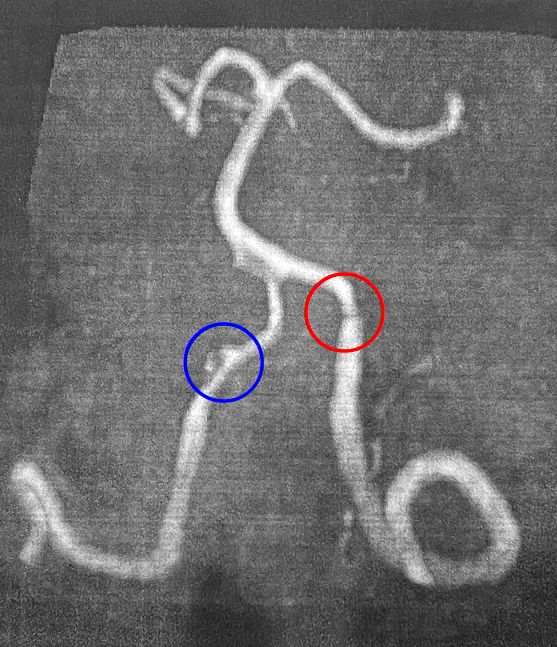

実際のMRI画像

青丸部分が疑わく思うれがちですが、解離は赤丸部分です。ちなみに、これを別の先生が診た場合、「うーん…」と唸って解離には触れない事が多いでしょう。「わからない」、あるいは「断定しかねる」となるのが普通です。

当院がこれを解離だと言うのは、多くの解離を診てきた経験があるからです。まず、出血がない解離があるという事を知らない先生が多いです。なぜなら解離は出血を裏付けとするため、<出血が確認できない=解離ではない>と判断するからです。